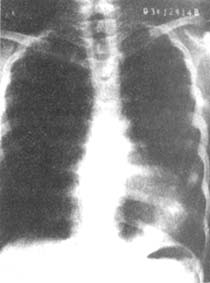

X線檢查可以見到肋骨的後部平直,前部向前下方急傾斜下降,心影多向左側胸腔移位,心影的中部有一個明顯的放射線半透明區(圖2),右心緣常與脊柱重疊,個別嚴重的患者心影可以完全位於左胸腔內,年齡較大的患者脊柱多有側彎。側位胸片可以看到胸骨體明顯向後彎曲,有的胸骨下端可以抵達脊柱前緣。

圖2漏斗胸的X線檢查

後前位照片:漏斗胸的心影中透明區